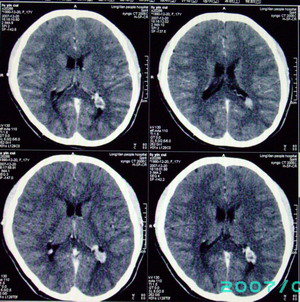

以下是引用九目段在2007-12-24 14:55:00的发言:[br]1,年轻女性[br]2,ct表现:左侧脑室三角区可见一不规则小明显强化的结节,中央见小低密度,侧脑室无扩张。[br]分析:[br]常见的有三种肿瘤好发三角区:[br]1,脉络丛乳头状瘤,好发于年轻者,明显强化,实性,分泌脑脊液,常伴有侧脑室扩大,肿瘤较小可以脑室扩大不明显,不能排除,但小结节尚不易形成坏死腔。[br]2,室管膜瘤,好发于儿童及青少年,明显强化,易坏死,大时伴脑室扩张。[br]3,脑膜瘤,明显强化,圆形,界请,无脑积水,一般不坏死。[br]诊断:[br]左侧脑室三角区结节,考虑室管膜瘤可能性大,不排除脉络丛乳头状瘤和脑膜瘤(因病史较长)。[br][br][本贴已被 九目段 于 2007-12-24 15:13:35 修改过]